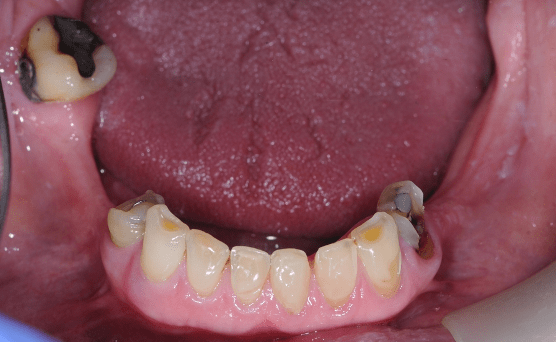

Partial dentures

Removable partial dentures can be provided to replace multiple missing teeth. This will aim to provide function for chewing and aesthetics by replacing the teeth. In this a simple replacement acrylic partial denture was provided.